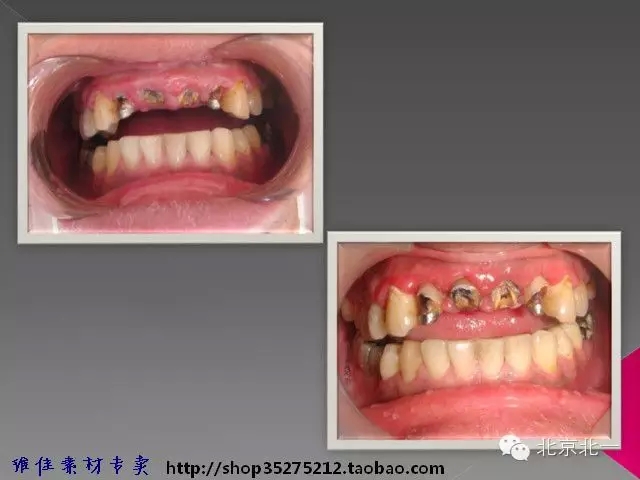

【牙周學(xué)習(xí)】冠延長手術(shù)